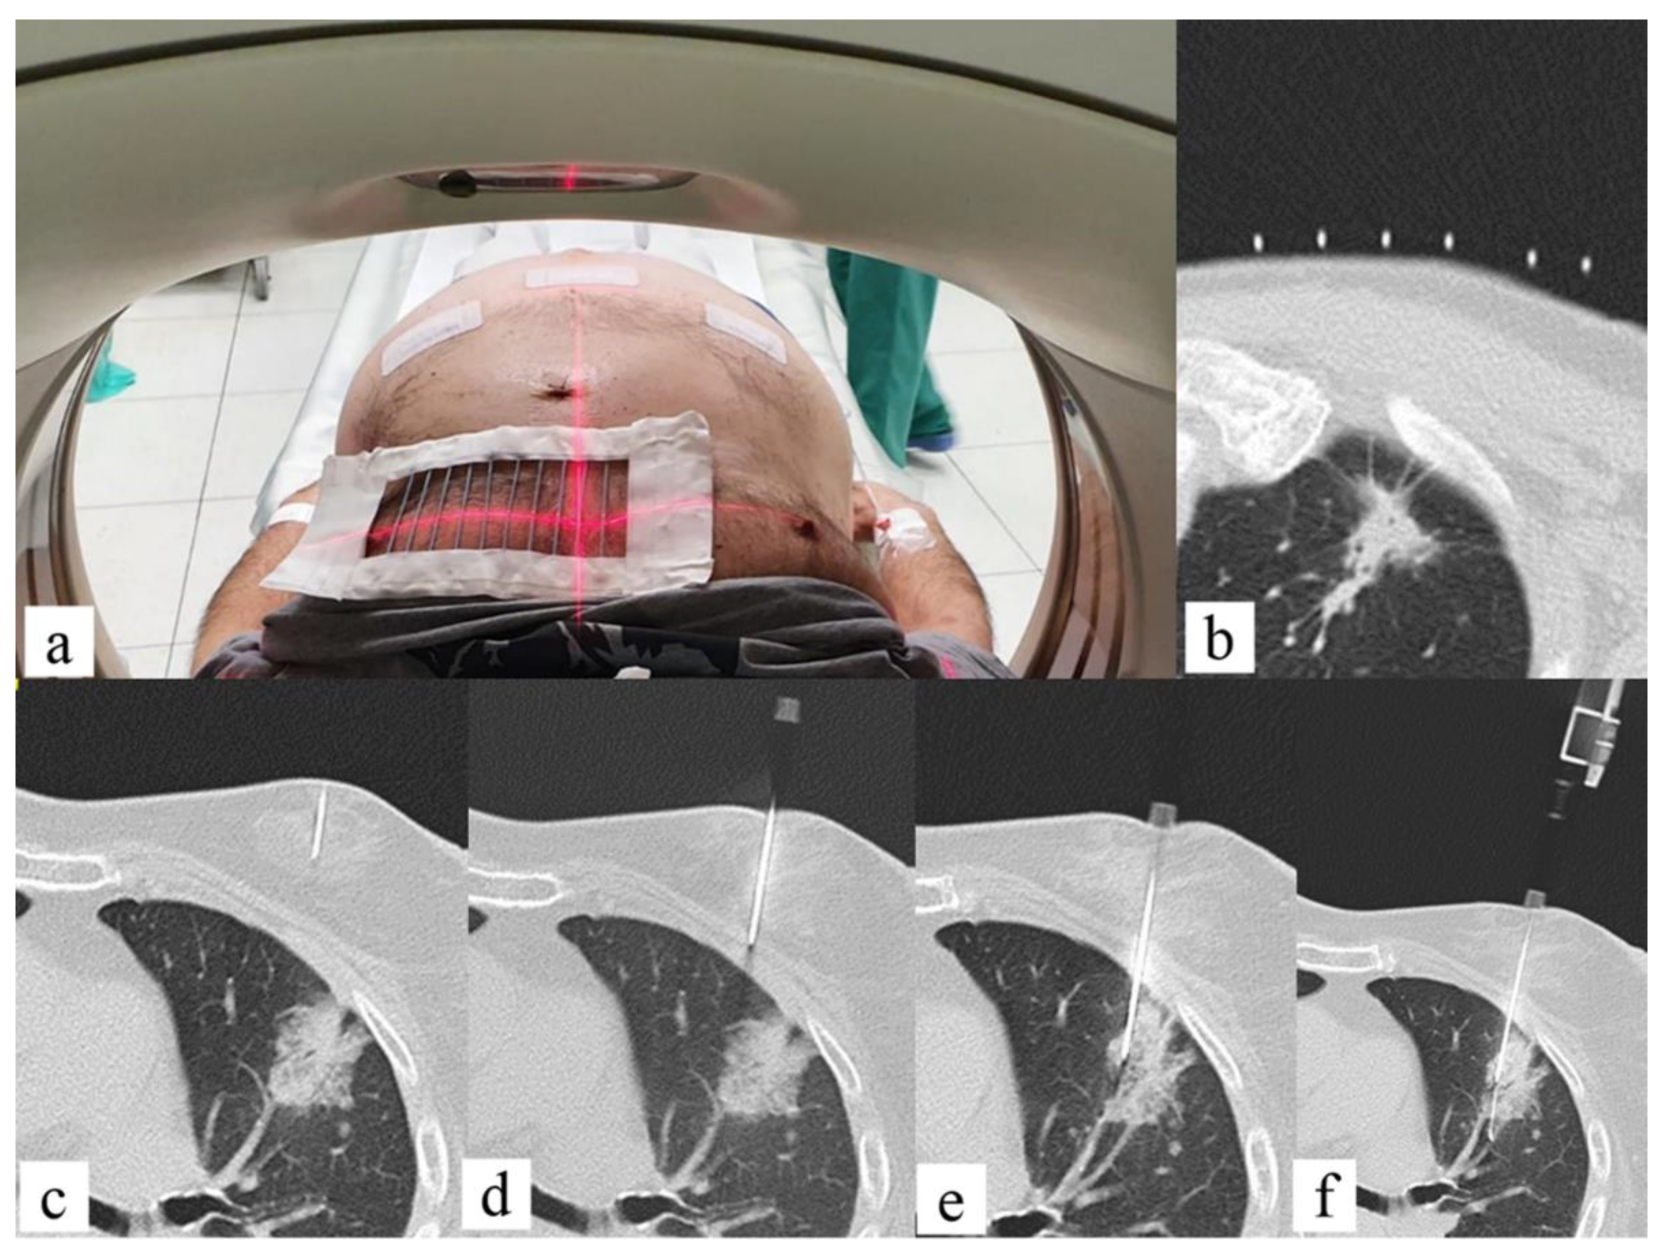

- Sabatino, V.; Russo, U.; D’Amuri, F.; Bevilacqua, A.; Pagnini, F.; Milanese, G.; Gentili, F.; Nizzoli, R.; Tiseo, M.; Pedrazzi, G.; et al. Pneumothorax and Pulmonary Hemorrhage after CT-Guided Lung Biopsy: Incidence, Clinical Significance and Correlation. Radiol. Med. 2021, 126, 170–177. [Google Scholar] [CrossRef]

- Faiella, E.; Messina, L.; Castiello, G.; Bernetti, C.; Pacella, G.; Altomare, C.; Andresciani, F.; Sarli, M.; Longo, F.; Crucitti, P.; et al. Augmented Reality 3D Navigation System for Percutaneous CT-Guided Pulmonary Ground-Glass Opacity Biopsies: A Comparison with the Standard CT-Guided Technique. J. Thorac. Dis. 2022, 14, 247–256. [Google Scholar] [CrossRef]

- Grasso, R.F.; Andresciani, F.; Altomare, C.; Pacella, G.; Castiello, G.; Carassiti, M.; Quattrocchi, C.C.; Faiella, E.; Beomonte Zobel, B. Lung Thermal Ablation: Comparison between an Augmented Reality Computed Tomography (CT) 3D Navigation System (SIRIO) and Standard CT-Guided Technique. Biology 2021, 10, 646. [Google Scholar] [CrossRef]